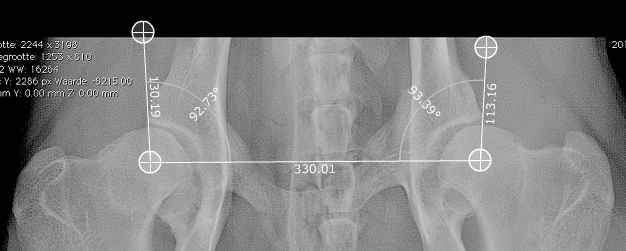

Ik ben Inge O niet maar ik kan het wel proberen. Eerst de Norbergwaarde:

Alles bij elkaar iets van 6, of zo. Echt erg laag.